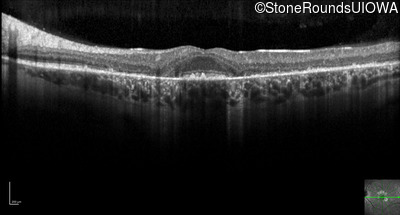

Optical Coherence Tomography - Left - 20/20 -2

Exemplar / OCT Stack

OCT Stack